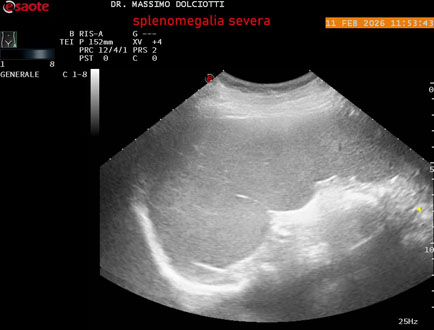

Data inserimento: 18/02/2026

Ecografia del: 11/02/2026

Strumento: Esaote MyLab Eight

Sonda: Conevx Multifrequenza 1-8 MHz

Età Paziente: F 68 anni

Motivazione dell'esame: follow up di splenomegalia.

Commento all'esame: le immagini ed il video documentano la milza con ecostruttura normale e morfovolumetria superiore alla norma, con diametro bipolare di 159 mm (v.n. 70-120 mm) ed area di sezione di 101 centimetri quadri (v.n. < 47 centimetri quadri).

Conclusioni: splenomegalia di severa entità (severe splenomegaly).